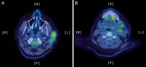

Paraganglioma or pheochromocytoma? A peculiar diagnosis

Ricardo Rodrigues Marques and others

Journal of Surgical Case Reports, Volume 2018, Issue 4, April 2018, rjy060, https://doi.org/10.1093/jscr/rjy060